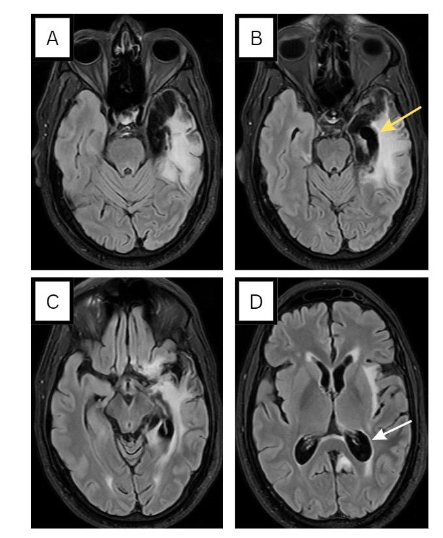

MRI was repeated and showed left temporal cortical/subcortical areas exhibiting encephalomalacia/gliosis (see Figure 4), with no evidence of restricted diffusion, thereby making stroke unlikely. An 18-channel awake EEG showed continuous focal epileptiform discharges over the left central parietal region, as quasi periodic discharges, over a background activity of moderate slowing (see Figure 5). This determination led to the diagnosis of postencephalitic non-convulsive status epilepticus. In light of this, the dosage of levetiracetam was escalated from 500mg BID to 1500mg BID. An EEG the following day showed resolution of status epilepticus but continued to display epileptiform discharges over the left fronto-central regions (Figure 6A). Consequently, lacosamide 200mg BID was introduced and EEG recorded 1 day later indicated the resolution of epileptiform discharges (Figure 6B). Upon discharge, the patient exhibited significant improvement in his clinical condition. Although he still experienced some baseline word-finding difficulty, his speech was notably more comprehensible. Additionally, he demonstrated no difficulty in responding to commands. It is important to note that the patient was an expatriate worker, and unfortunately there was loss to follow-up post-discharge.

In a retrospective review of patients with prior HSVE, postencephalitic epilepsy was noted in 45.5% of the patients. The predominant seizure patterns in postencephalitic epilepsy were unilateral temporal, bilateral temporal and multifocal or generalized with the majority of patients reporting an aura. The high incidence of late unprovoked seizures following HSE may be due to the necrotizing nature of HSV-1 infection and involvement of the highly epileptogenic mesial temporal and basi-frontal cortices. For example our patient’s repeat MRI scan showed the devastating impacts HSV can have on the brain including the profound atrophy of the left mesial temporal regions.